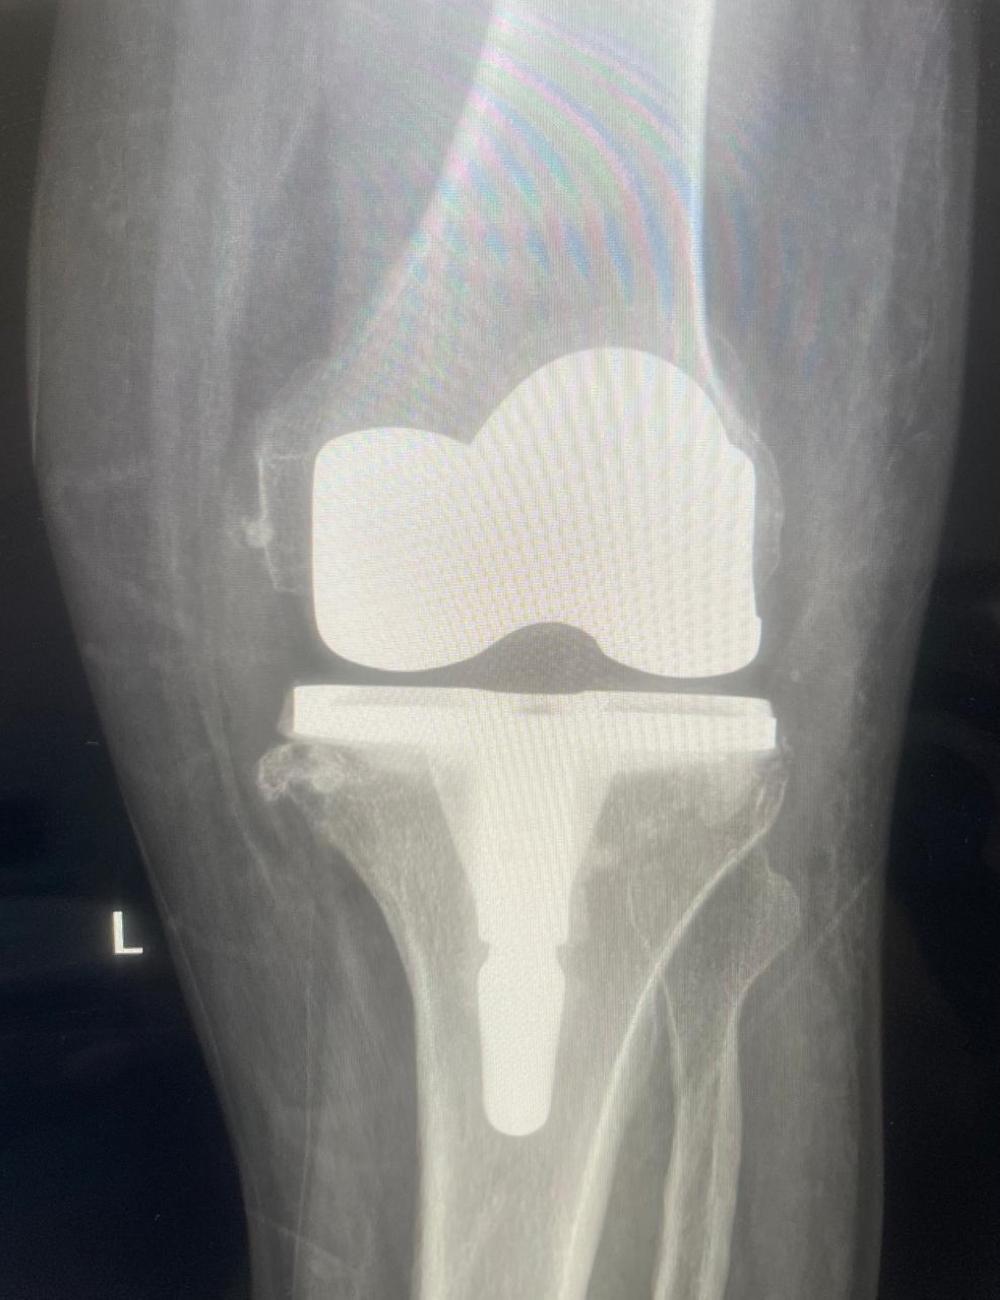

أطلق مستشفى القطيف المركزي وحدة تخصصية لتبديل وترميم المفاصل، معلناً عن إجراء 30 عملية ناجحة لمفصل الركبة وفق المعايير العالمية، لتعزيز الخدمات الجراحية الدقيقة والارتقاء بجودة حياة المرضى بالمنطقة الشرقية.

وكشف المستشفى عن نجاح الطواقم الطبية في إجراء 30 عملية جراحية لتبديل مفصل الركبة منذ انطلاق الوحدة، معتمداً أحدث الممارسات والبروتوكولات الطبية المعتمدة في هذا المجال.

وأشار إلى أن هذه النتائج الإيجابية تعكس الجاهزية العالية للكوادر الجراحية وتوفر التقنيات الطبية المتطورة التي تضمن سلامة ودقة الإجراءات التداخلية.

وأوضح المستشفى أن الوحدة تقدم حزمة خدمات طبية متكاملة، تبدأ من تقييم وتشخيص حالات تآكل المفاصل والإصابات المزمنة، وصولاً إلى التدخل الجراحي الدقيق لترميم المفاصل.